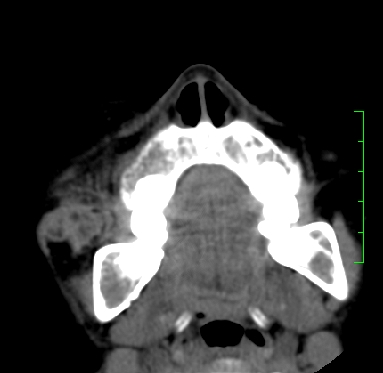

标题: PED1889:上颌窦病变

m,10y,外伤做ct